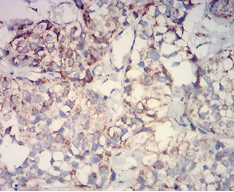

IHC    1/200 - 1/1000